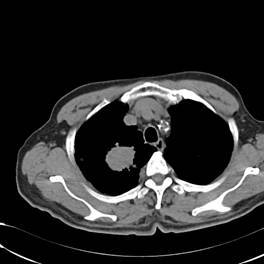

典型病例1:患者鞠xx,女,68岁,住院号:488141,因左胸痛1月余入院。2015年3月31日胸部增强CT示:左肺下叶2.5cmx2.8cm占位,左侧第三前肋骨溶骨性转移、形成厚约3cm肿块,左侧腋窝淋巴结2.1cmx4.1cm及前纵膈淋巴结转移。患者于2015年4月1日经CT引导下穿刺活检、病理证实为左肺下叶腺癌。于2015年4月5日对其采用125I放射性粒子置入治疗。治疗3个月随访,患者胸痛缓解,左肺下叶原发病灶消失,粒子聚集;左侧第三前肋骨基本恢复正常形态;前纵膈淋巴结消失,粒子聚集;左侧腋窝淋巴结缩小2/3。目前患者生活质量良好,可从事一般家务劳动。

术后三个月CT片: